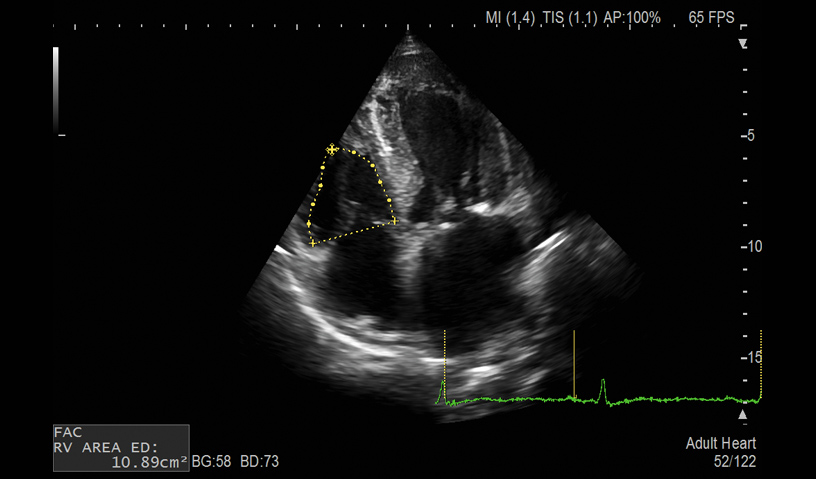

FAC

- Auto LV, LA and RA Volume and FAC